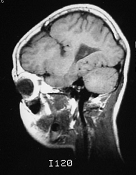

Mapeamento cerebral com EEG para estudo do aprendizado da leitura

Diagnóstico